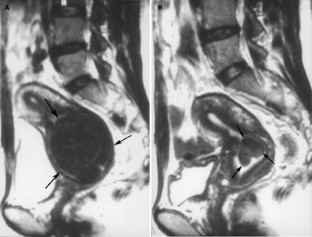

Figure 1A, B